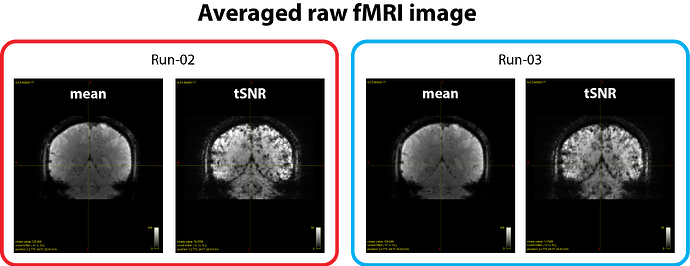

During acquisition, we did not use prescan normalization, so the raw fMRI data naturally show an intensity bias, as expected (see figure 1 below).

We verified that the raw and other preprocessed images appear consistent across runs:

- Averaged raw fMRI images show comparable intensity bias levels (see figure 1).

- tSNR maps look similar across runs (see figure 1 and 2).